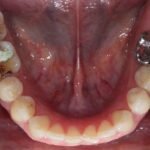

Punto Bajío Casos Clínicos Prótesis Fija sobre Implante unitario Inicio Provisional Final Prótesis Parcial Fija sobre 2 Implantes 2 Implantes Final Prótesis Bucal Removible Inicial Inicial Superior Inicial Inferior Rayos X Inicial Rayos X Inicial Frontal Final Final Superior Final Inferior Prótesis Parcial Fija/ Coronas de Circonio Sonrisa Inicial Foto Inicial Foto Inicial Inferior Foto Final Inferior Foto Final Sonrisa Final Prótesis Total Protesis Inmediatas 1 Protesis Inmediatas 2 Prótesis Removible/ Coronas Metal-Ceramica Carillas Incrustaciones Endodoncia